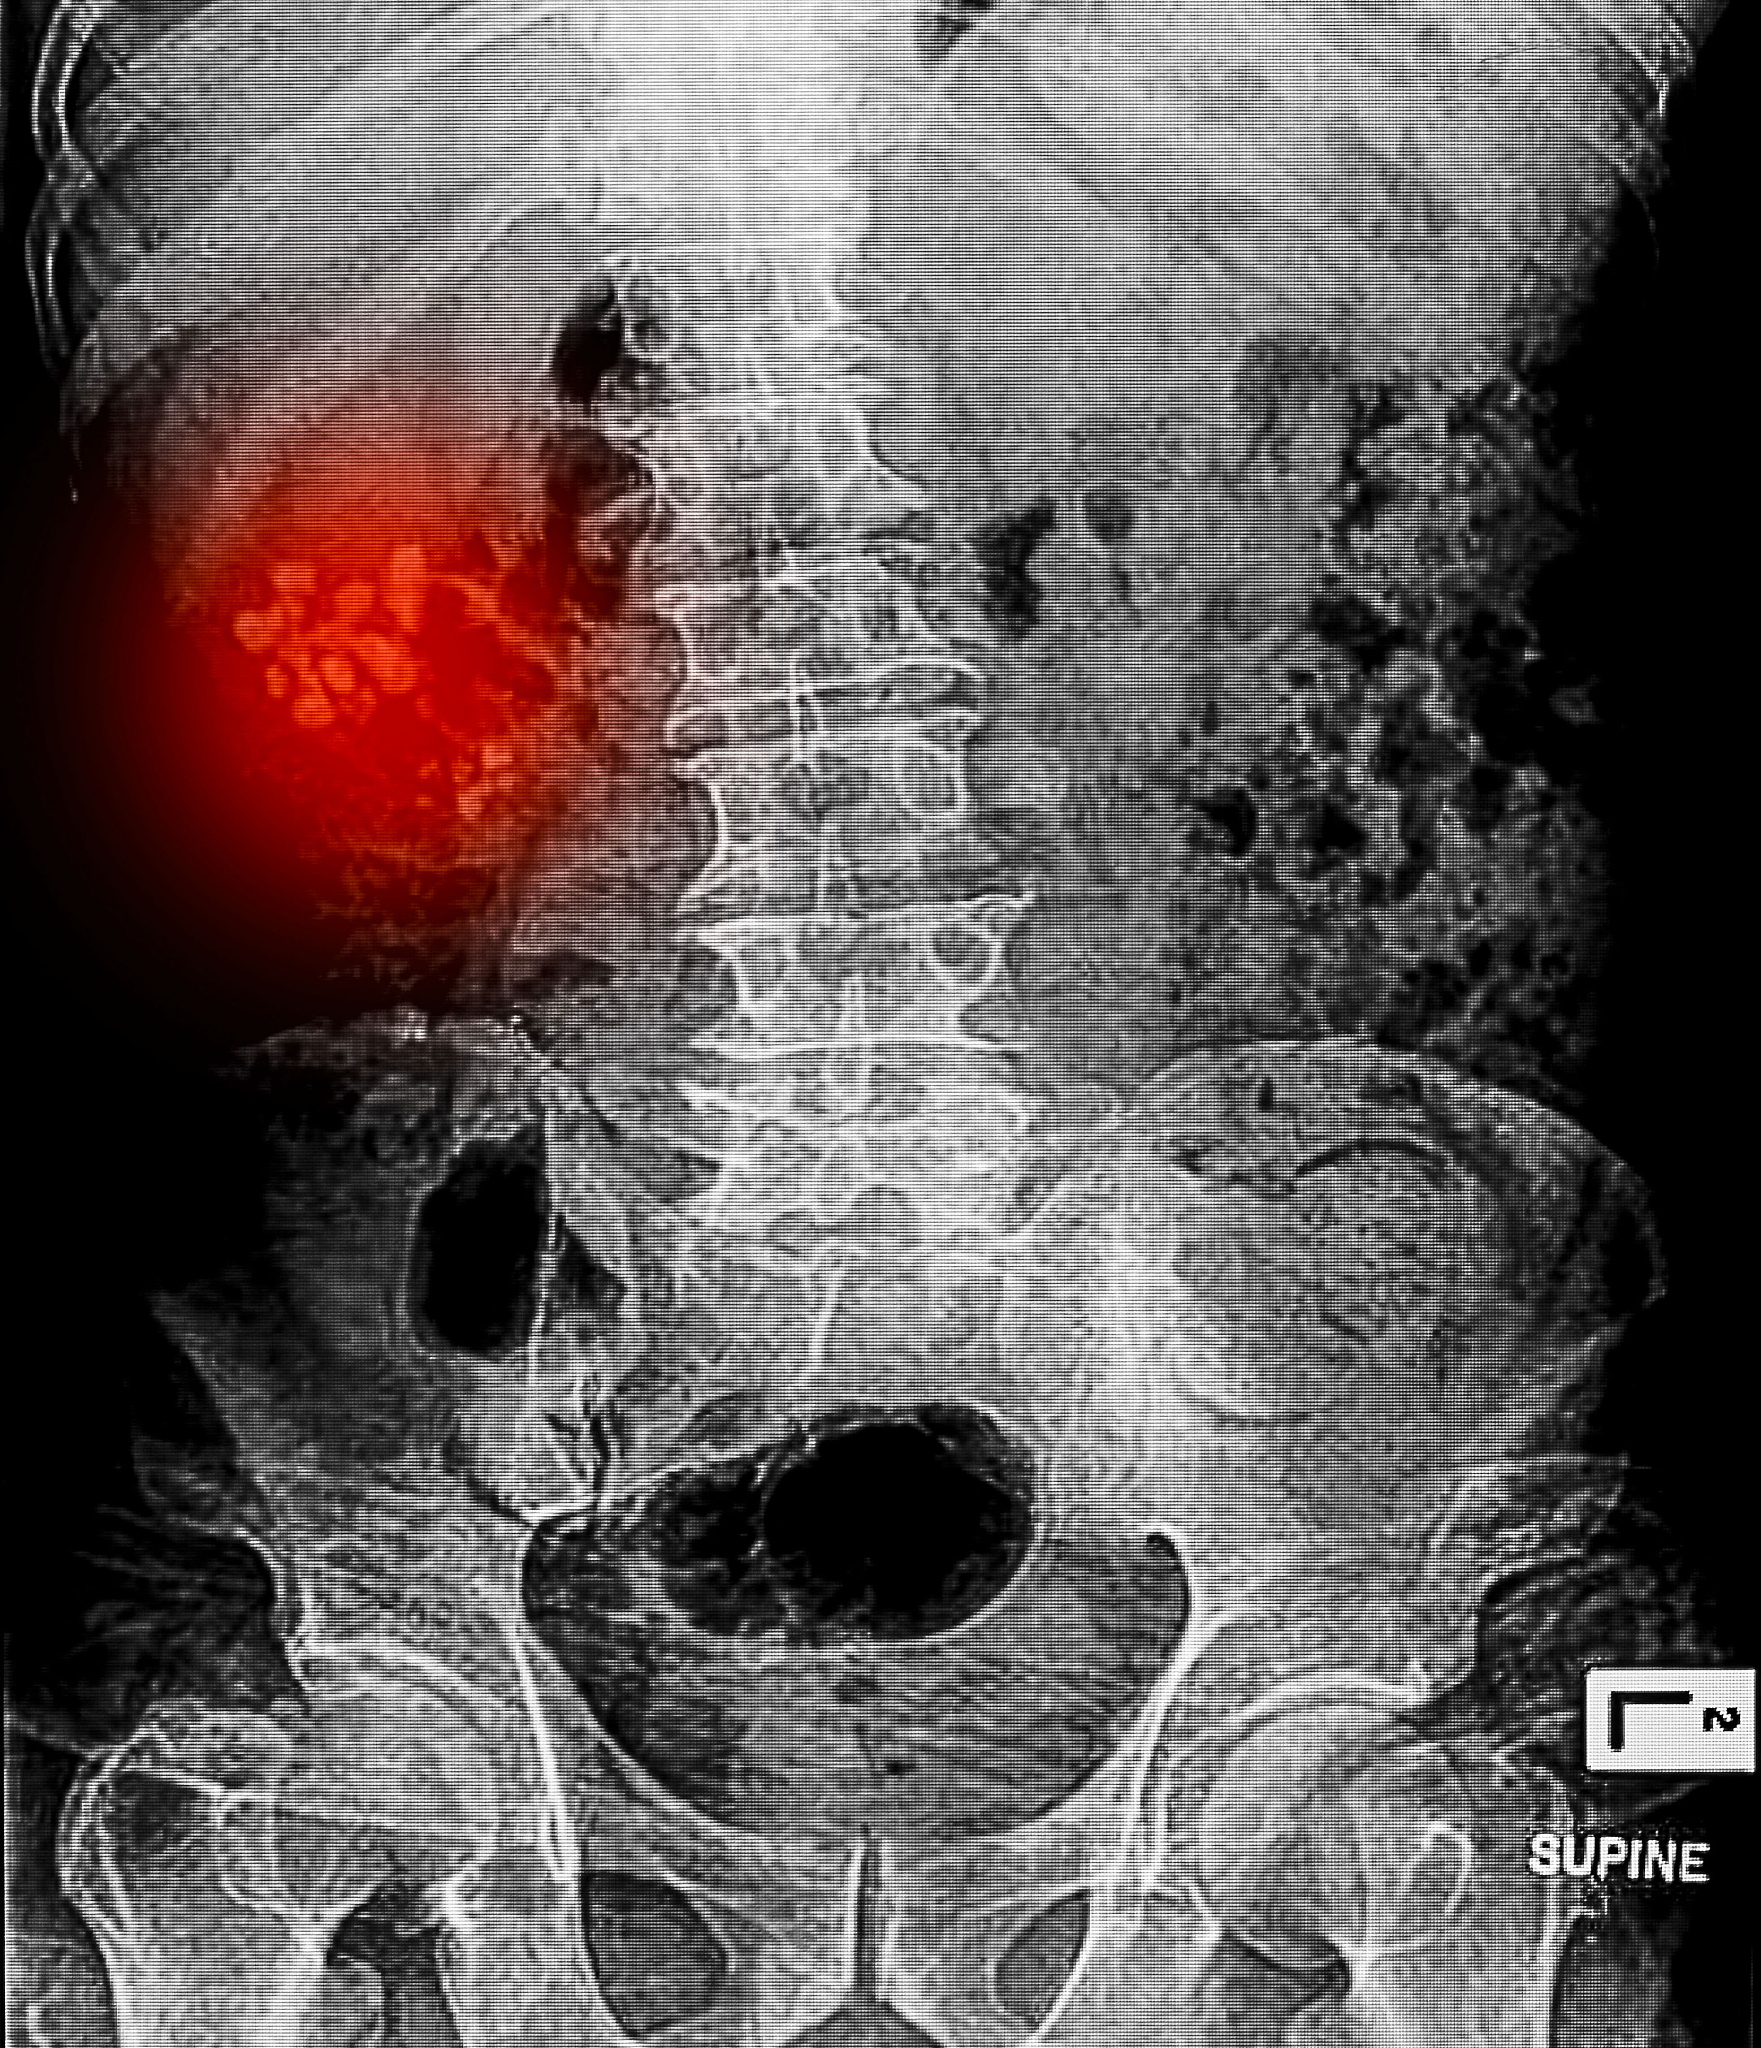

肾结石是一种常见疾病,指尿液中的物质在肾脏或尿路中形成的固体结晶。这些结晶通常由钙、尿酸、草酸等物质构成,大小不等,小的如沙粒,大的可达数厘米。

肾结石的治疗方法取决于结石的大小、位置、数量和患者的具体情况。常见的治疗方法包括:

• 保守治疗: 对于较小的结石,可以通过多饮水、调整饮食、服用药物等方法促进其排出。* 体外冲击波碎石术 (ESWL): 使用冲击波将结石击碎成小颗粒,使其更容易排出。* 输尿管镜碎石术: 将输尿管镜经尿道插入,直达结石部位,然后使用激光或其他碎石设备将结石击碎。* 经皮肾镜碎石取石术: 在腰部开一小切口,将肾镜插入肾脏,直视下将结石击碎取出。* 开放手术: 对于巨大的肾结石或其他治疗方法无效的情况,可能需要进行开放手术治疗。